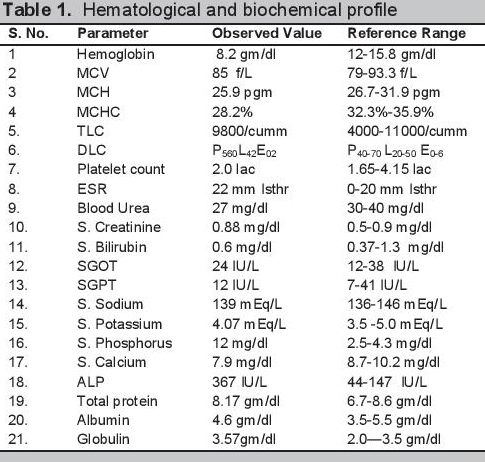

Biochemical evaluation revealed microcytic hypochromic anemia, hypocalcemia and hyperphosphatemia (Table 1). The hormonal investigations were done through chemiluminescence immunoassay by Abbott ARCHITECT i1000sr immunoassay analyzer USA using fasting plasma sample which revealed elevated parathormone level, autoimmune hypothyroidism, hypergonadotropic hypogonadism along with raised prolactin (Table 2). Roentgenographical assessment revealed bilateral short 3rd, 4th and 5th metacarpals and metatarsals with positive Archibald sign [Figure 3a,b] while the rest of the skeletal survey was normal. Ultrasonography of the abdomen showed streak ovaries along with pre-pubertal uterus. Her karyotype showing 45 (X,O) confirmed the diagnosis of Turner syndrome. Electrocardiography, 2D echocardiography and pure tone audiometry were unremarkable while thyroid ultrasonography revealed hypo-echogenicity of the thyroid gland.

Click here to download Table 1Table 1.Hematological and biochemical profile

PHP is a heterogeneous disorder with a variety of manifestations. The prevalence of the disorder is about 0.79 per 100,000.[1] It was the first hormone resistance syndrome ever described. The first description of pseudohypoparathyroidism with Albright hereditary osteodystrophy was made in 1942 by Fuller Albright.[5] In his original work, Albright described a person with hypocalcemia and hyperphosphatemia with normal renal function who had no calcemic and phosphaturic response to bovine parathyroid extract as compared to hypoparathyroid patients, hence the concept of hormone resistance came into being.[5] Later on, with the discovery of the PTH receptor and its mechanism of action, the basic pathophysiology of the disorder was described and the syndrome was further subdivided into various types.[1] The primary pathological mechanism was described as a GNAS mutation which leads to defective activity of Gsα (stimulatory subunit of G protein coupled receptors).[1] PHP has various manifestations due to the involvement of maternal imprinting of the genes.[1] PHP 1a is characterized by parathormone resistance (elevated PTH in spite of hypocalcemia and hyperphosphatemia; poor cAMP and phosphaturic response to exogenous PTH administration) along with features of Albright’s hereditary osteodystrophy (AHO), characterized by brachydactyly, rounded face, short stature, central obesity, subcutaneous calcifications in conjunction with variable mental retardation.[1] Together with variable PTH resistance, resistance to other hormones operating through G protein coupled receptors can also be present in PHP.[1] The patient in the present case had short stature, a round face, brachydactyly [Figures 1 and 2a,b] and elevated PTH in spite of hypocalcemia and hyperphosphatemia (Table 1). Along with these features, the patient also had delayed puberty and no development of secondary sexual characteristics due to hypergonadotropic hypogonadism. Her skeletal survey showed specific changes associated with AHO such as short 3rd, 4th and 5th metacarpals with short distal phalange of her thumb but the absence of heterotropic calcification.

In our patient, the presence of hypocalcemia, hyperphosphatemia, elevated PTH level along with the normal renal functions and 25(OH) vitamin D levels clearly point towards PHP as the differential diagnosis. Presence of the AHO phenotype points towards the possibility of PHP 1a, 1c and pseudopseudohypoparathyroidism. The presence of AHO along with biochemical abnormalities, presence of renal PTH resistance leaves no other differential diagnosis except PHP 1a and 1c.[1] The Gsα activity analysis further differentiates between PHP 1a and PHP 1c but in the present case, genetic analysis and response to exogenous parathormone could not be done due to financial constraints and lack of available facilities. In the view of clinical history, examination, biochemical, radiological and karyotypic findings, the diagnosis of Turner syndrome with PHP with autoimmune hypothyroidism and microcytic hypochromic anemia was made. The patient was started with calcium, calcitriol, haematinics, thyroxine and estradiol with follow up advice after 2 months. After 2 months of starting therapy, the patient improved clinically and biochemically.